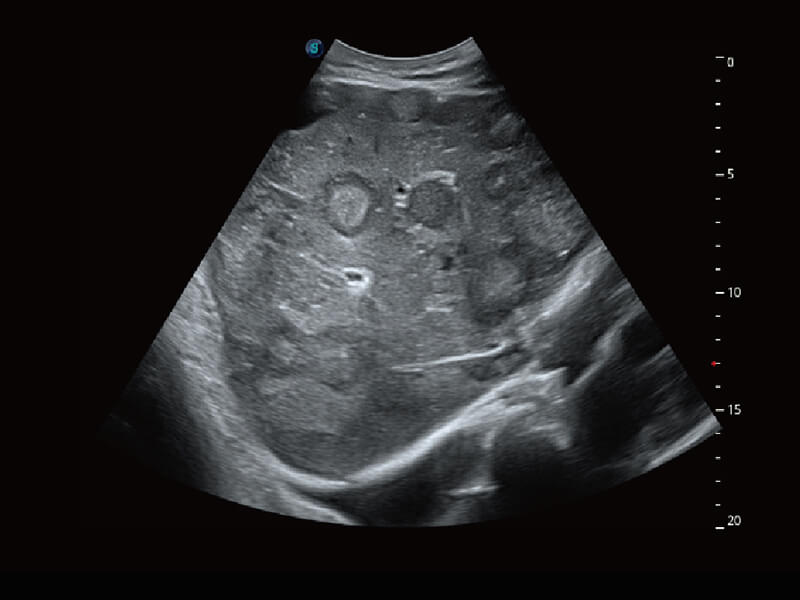

S60探头工艺,从前端信号处理每一个环节采集无损声学数据,真实还原组织原貌,再现解剖细节。

• 腹部单晶体探头( C1-6A )